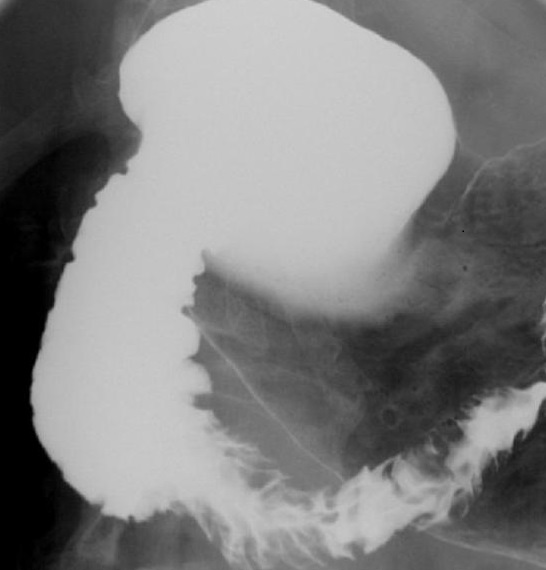

La TOGD (

transit gastro duodenale baryte ) : Les tumeurs

adenocarcinoma de la tete du pancreas est le plus souvent

deformer la tete et region corporeal - caudale , ce qui entraine

de deformer et elargissement de arcade duodenal D1 , D2 et souvent en

numero 3 inverse (signe de

Frostburg).

Image radiologique TOGD

baryte en decubitus ventrale d'une adenocarcinoma de

la tete du pancreas . Arcade duodeal est

elargir et se deformer en numero 3 inverse ( signe

de Frosbourg ) |

Meme cas en OAD . Arcade duodenum

est elargir et se deforme de compresse a droit et en

avant |